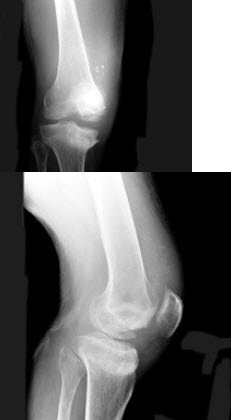

E.肺淤血

246、单项选择题

女,53岁,因摔倒时手掌着地,感右肘关节肿痛、畸形,X线摄片如图所示,正确的诊断是()

A.右肱骨外髁骨折

B.右肱骨内上髁骨折

C.右肱骨外上髁骨折

D.右肱骨小头骨骺分离

E.以上均不正确